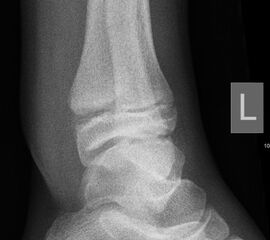

Mediale Malleolarfrakturen

Bei den medialen Malleolarfrakturen handelt es sich um Fugengelenkfrakturen bzw. Aitken II und III Verletzungen. Kennzeichnend ist, dass der Frakturverlauf die wachstumsaktive Zone zur Epiphyse hin durchkreuzt. Die Verletzung der wachstumsaktiven Zone macht diese Verletzungen besonders problematisch.

Fugengelenkfrakturen treten typischerweise vor dem 10. Lebensjahr auf, in einer Phase, in welcher die Wachstumsfugen noch weit offen sind. Dieser Frakturtyp betrifft fast ausschließlich den medialen Malleolus. Laterale Frakturen sind extrem selten, teilweise kommt es zu lateralen Bandverletzungen oder Fugenschaftfrakturen der distalen Fibula. Die Frakturlinie verläuft in einer Verlängerungslinie von der medialen Taluskante nach proximal. Häufig stellen sich Verletzungen des Innenknöchels im Röntgenbild schlechter dar, insbesondere wenn die Aufnahmen verdreht sind oder die Ebene der Fraktur bei geringer Dislokation verkippt zur Röntgenebene liegt. Besteht klinisch der geringste Hinweis auf eine Verletzung des Innenknöchels, muss aufgrund der Tragweite der Verletzung durch entsprechende Aufnahmen gegebenenfalls auch Schnittbildverfahren die Verletzung sicher diagnostiziert oder ausgeschlossen werden (Abb. 15).